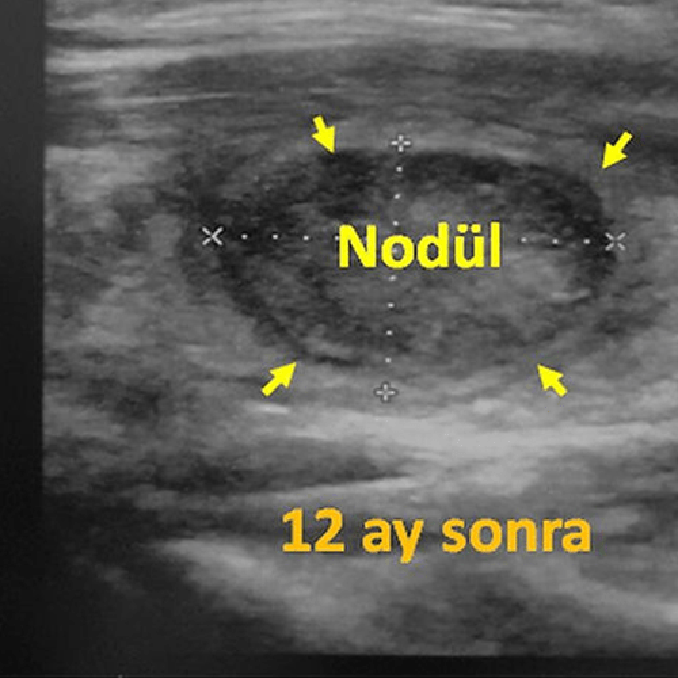

Sol tiroid lobunda 10 cm çaplı iyi huylu solid nodülü olan 31 yaşındaki erkek hastamıza embolizasyon tedavisi uygulandı. Altı ay sonra, nodülün hacmi %90 oranında azalmış ve boynun görünümü normale dönmüştür.